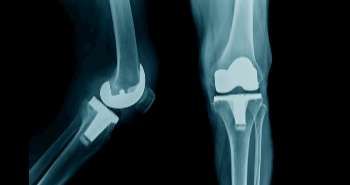

Skewed bone cement distribution, a high proportion of bone cement volume to vertebral body volume and abnormal BMD is considered as the significant risk factors to cause SNVCF as per the reports a recently published analysis. Secondary new vertebral compression fractures (SNVCFs) involved two types of fractures; adjacent vertebral compression fractures (AVCFs) and remote vertebral compression fractures.

A total of 402 patients were assessed over a minimum follow-up of 4 years after PVP to extract data regarding the relationship of SNVCFs with radiological, clinical and PVP procedure-associated morphologic parameters. A three-dimensional voxel-based analysis was applied to evaluate the procedure-associated morphologic parameters. Multivariate and univariate regression analyses were directed. On univariate analysis, both AVCF and SNVCF showed a significant relationship with preoperative sagittal index (SI), bone mineral density (BMD), intradiscal bone cement leakage, and preoperative compression ratio, whereas, remote vertebral compression fracture only correlated with preoperative SI and BMD. Skewed bone cement distribution along the inferior-to-superior axis and a large proportion of bone cement volume to vertebral body volume considered as the significant risk factors for AVCF. On multivariate analysis, AVCF showed considerable correlation with upper adjacent intradiscal bone cement leakage and SNVCF with BMD. As per the findings, low BMD, high preoperative compression ratio, and high preoperative SI are the factors used to predict the SNVCF. The bone cement should be injected symmetrically and evenly through the inferior-to-superior axis, and the volume of relative bone cement should not be excessive to avoid upper adjacent intradiscal leakage. BMD correction should also be considered as an essential aspect to control SNVCF.